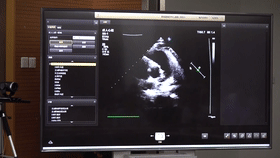

5G遠程會診現(xiàn)場,西安國際醫(yī)學(xué)中心心內(nèi)科張衛(wèi)澤主任、超聲科陳姍姍主任打開4K高清顯示器,屏幕上立刻出現(xiàn)了商洛國際醫(yī)學(xué)中心的B超畫面,一位醫(yī)生正在為患者做心臟B超,隨著探頭的轉(zhuǎn)動,超聲機器上的畫面清晰可見,雖然兩家醫(yī)院相距一百多公里,但畫面流暢,沒一點拖沓。

“真的太棒了”張衛(wèi)澤表示,“沒有延時與卡頓,清晰的好像在一個房間內(nèi)進行病歷討論”。陳姍姍非常興奮,直呼很震撼。她告訴筆者,“以前做遠程會診,經(jīng)常遇到畫面和聲音不在一個頻道、畫面模糊等情況,遇到疑難病歷只能將影像拷下來回去研究,現(xiàn)在好了這些問題都將一次性解決。”